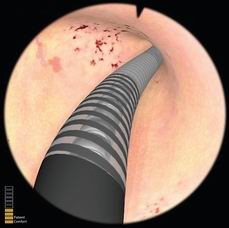

子宫内膜去除模块

可练习如何使用滚球电极,进行子宫内膜去除术的操作